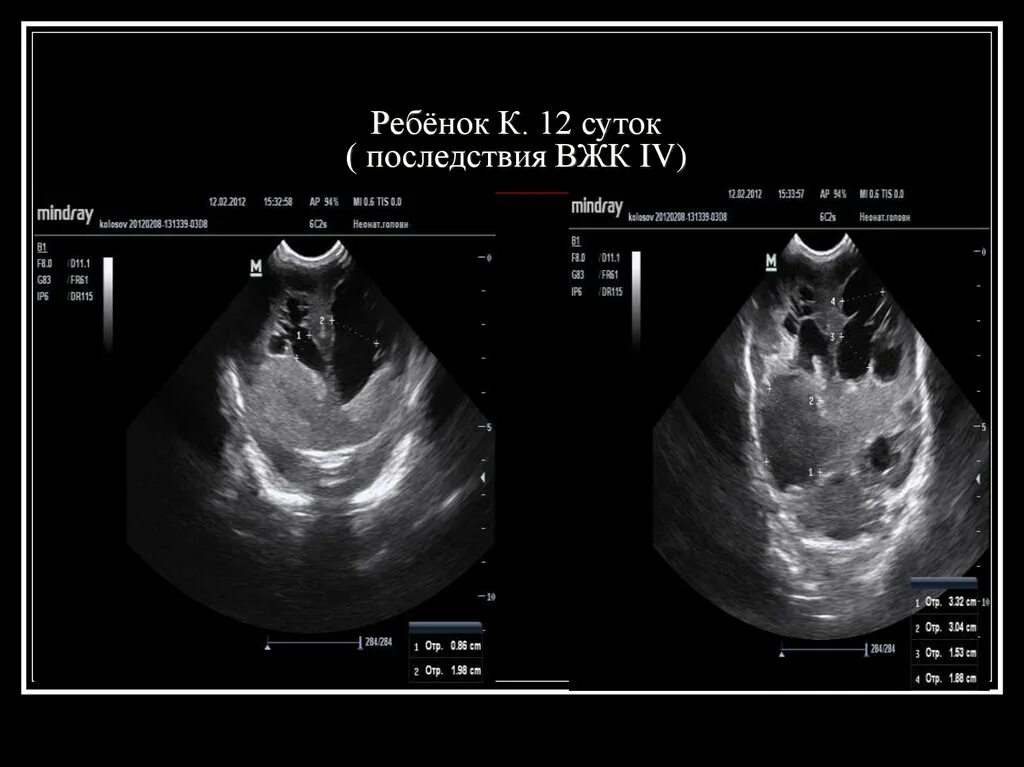

Кровоизлияние в мозг у новорожденного степени